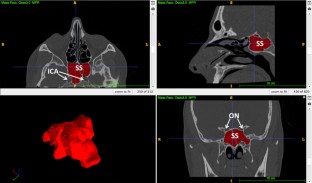

Relationship between sphenoid sinus volume and protrusion of internal carotid artery and optic nerve: a 3D segmentation study on maxillofacial CT-scans

Anatomy of sphenoid sinuses has acquired a growing importance with the diffusion of transsphenoidal surgical procedures. A common risk in these practices is the damage of internal carotid artery (ICA) and optic nerve (ON), which may protrude into the sphenoid air cavities. This study aims at analysing the relationships between sphenoid sinuses volume and protrusion of ICA and ON.

260 head CT-scans were retrospectively analysed (equally divided among males and females, age range 20–92 years). Volume was segmented through ITK-SNAP software. In addition, the subjects were classified into four groups: no protrusion of any structure (group 1), protrusion of ICA (group 2), protrusion of ON (group 3), protrusion of both ICA and ON (group 4). Possible statistically significant differences in prevalence of the four groups according to gender were assessed through Chi-squared test (p < 0.05). Differences in volume between the four groups were assessed through one-way ANOVA test (p < 0.05), separately for males and females.

Group 1 was the most frequent (40.0%), followed by group 4 (27.7%) and group 2 (18.5%), without any difference according to gender. For what concerns volume, cases of ICA and concomitant ICA + ON protrusion had significantly larger sinuses, whereas isolated ON protrusion did not modify sinus volume.

Results show that protrusion of ICA is positively related with the volume of sphenoid sinuses, whereas the same relation was not verified for ON: surgeons should accurately consider possible ON protrusion in each case, as it may occur independently from sphenoid sinuses volume.